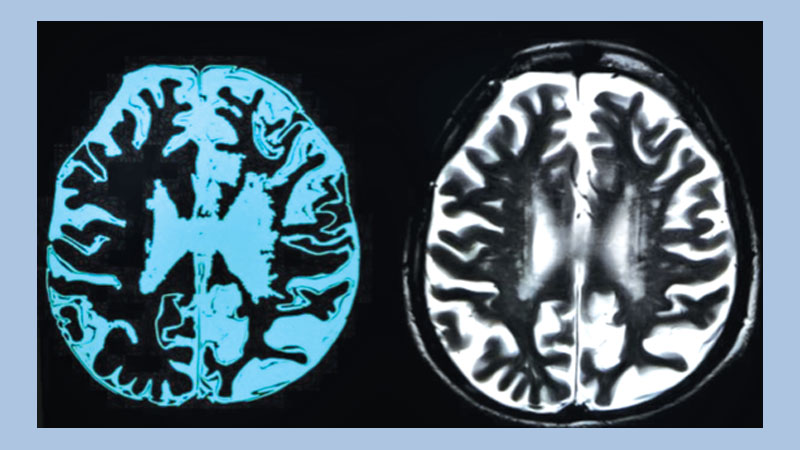

Aducanumab targets a protein called amyloid that forms abnormal deposits the brains of people with Alzheimer's. Scientists think these plaques are toxic to brain cells and that clearing them using drugs would be a massive advance in dementia treatment, although not a cure.